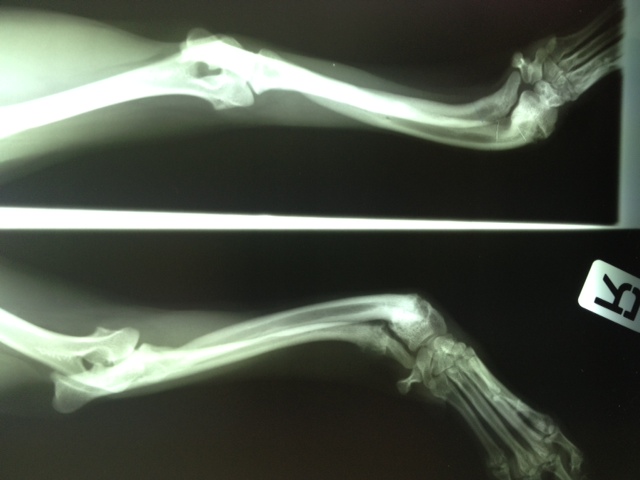

Felipas erste Operation

06Heute hatte Felipa ihren ersten OP-Termin.

Wir waren alle sehr aufgeregt. Und selbst der erfahrene Arzt meinte, es sei eine ungewöhnliche Aktion, denn normalerweise weist nur ein Pfötchen so starke Anomalien auf. Er hatte es noch nicht, dass beide operiert werden müssen.

Felipa war relativ unbeeindruckt von der ganzen Geschichte und tanzte schon kurz nach dem Eingriff wieder auf dem Tisch herum.

In sechs Wochen erfolgt dann die zweite OP.